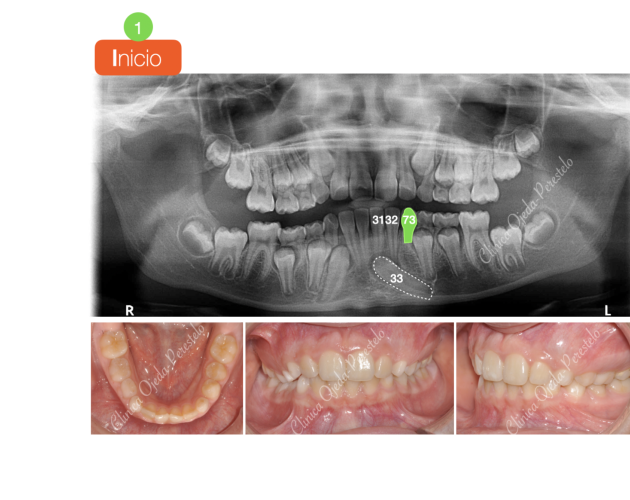

Canino Mandibular Retenido (33) Casos de Éxito - Dientes Retenidos